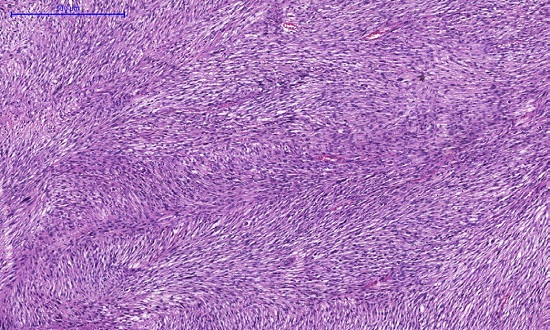

O exame histopatológico revelou neoplasia mesenquimal ulcerada, composta de células fusiformes e epitelioides, com pleomorfismo nuclear e atividade mitótica acentuada (Figuras 4 to 5), caracterizando MFH, de alto grau histológico. O painel imuno-histoquímico do tumor mostrou positividade para CD68 (Figura 6) e negatividade para p63, AE1/E3, CK5/6, MELAN A, CD34, AML e S100, SOX-10.

A histopatologia revela células fusiformes pleomórficas dispostas em feixes comuns, padrão estoriforme, podendo ser encontrados histiócitos multinucleados, infiltrados em derme profunda e tecido celular subcutâneo.15,16

O MFH apresenta imunorreatividade para vimentina e CD68 (marcador histiocítico).17,18 S100, desmina, S-100 e HMB-45 são anticorpos encontrados no lipossarcoma ou nervo periférico maligno, tumor de bainha, rabdomiossarcoma e melanoma maligno, respectivamente, ao passo que CD34 mostra reatividade em angiossarcomas.15,16